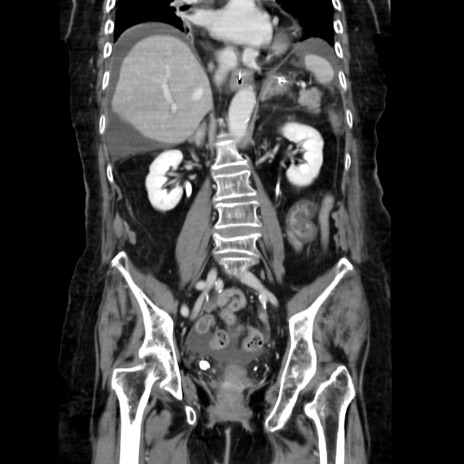

症例40(冠状断像)

【症例】90歳代女性

【主訴】腹痛・嘔吐

【現病歴】 食欲低下、嘔吐があり昨日他院受診。肺炎と診断され入院となる。入院後より腹部全体に圧痛あり。胃管留置され経過みていたが、症状持続するため、

当院転院となる。

【既往歴】胸椎圧迫骨折、胆石症

【身体所見】腹部:中央に激痛あり、圧痛あり、反跳痛不明

【データ】WBC 17100、CRP 18.82

冠状断像